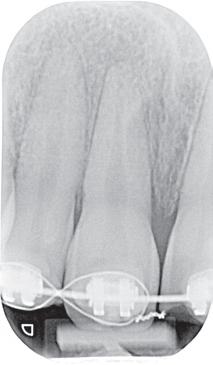

Röntgenologisch onderzoek

Er is gekozen voor vervaardiging van een OPT-opname (afbeelding 5) met als rechtvaardiging te controleren op fracturen van de kaak. De patiënt kwam immers niet in maximale occlusie. Hoewel een CBCT aanwezig is in de praktijk, was er naar mijn mening geen rechtvaardiging voor deze opname op dit moment. Fracturen zijn immers ook zichtbaar op een OPT, en bovendien moest er nog worden gereponeerd, wat van invloed kan zijn op het peri-apicale gebied. Ook na reponeren was naar mijn mening een CBCT

(+/- = neutraal/normaal sensibel)

niet gerechtvaardigd, omdat pulpa diagnostiek in de opvolgende traumacontroles hierin een essentiële rol spelen. Daarnaast had een CBCT mijn behandeling niet beïnvloed en vandaar de keuze voor een OPT. Op afbeelding 5 is door mij volgende waargenomen:

• 41, 32 licht verbrede parodontaalspleet.

• Onderlip geen radiopaciteiten.

Tijdens het uitvoeren van het onderzoek leek alsof elementen 11 en 21 geen mobiliteit vertoonden en tegelijkertijd was het duidelijk dat ze niet in de juiste positie stonden. In een dergelijk geval, waarbij enige druk nodig is om te reponeren, is het fijn om te weten waar de elementen horen te staan. Het niet in de juiste positie brengen kan zorgen voor een (blijvend) suboptimaal resultaat of een extra lang behandeltraject. Op het moment dat ik bezig was met de vraag ‘Waar horen ze te staan?’, zag ik onze intra-oraal scanner staan en toeval wilde dat er al snel een scan uit 2023 aanwezig was. Deze was gemaakt net na het